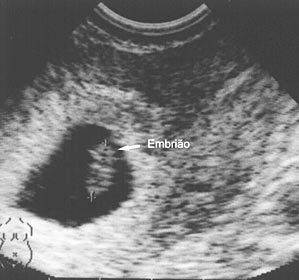

Semana 6

O bebê O coração do bebê está em desenvolvimento e formam-se as quatro cavidades.. O bebê já mede entre 8 e 11 mm.